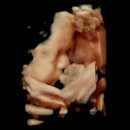

• 눈부신 헤어 | 만삭사진 옷 촬영 솔직 후기 눈부신 일상 강남점

3. 가능한 평일에 일정 예약하는 걸 추천드려요. 평일 촬영 시 무료로 아빠 헤어메이크업 해주고 스튜디오가 덜 바빠서 여유롭게 촬영할 수 있답니다. ​ ​ ​ ​ 다만...이벤트 참여 시 대응이 너무 느리고 소통이 어려웠어요.😔 ​ SNS와 카페에 후기 남기면 5x7인치 액자 증정해주는 행사였는데 아무리 무료 이벤트라 하더라도...

• 눈부신 헤어 | [임신 31주차] 라테라 산후조리원 연계 눈부신일상 목동 만삭촬영 후기+성장앨범 계약

귀찮기도 하고 전문가가 찍어주는게 더 낫겠지 싶어서 그냥 예약함 그리고.... 결국 안하려고 했던 성장앨범까지 계약하고 오게 되는데^^... 후기 렛츠꼬.. 눈부신일상 목동점 만삭촬영 사전 준비사항 만삭촬영 준비사항 ✔️ 촬영 40분전에 도착해야 메이크업 서비스 가능 ✔️ 파운데이션까지 하고 오기, 헤어도 직접 하기...

• 눈부신 헤어 | 눈부신 일상 이천점(마리나 산부인과 연계)만삭사진과 성장앨범 계약후기

옷도 제공 된다는거. 마땅이 여성스럽고 무난한 옷이없었데 아주 굿굿! ​ 예전에 상호가 다른 곳이었는데, 베이피 파스텔과 합병됐다더라. 그치만 상호명은 [눈부신 일상] 이고, 강남과 청주에도 있었다. 사진 찍기 전에 네이버 카페 초대 받아 컨셉을 정하고 와달라고 했다. ​ ​ 9년전에 찍었던 만삭사진 ​ 헤어와 메이크업...

• 눈부신 헤어 | 눈부신일상 청주점 | 무료만삭촬영 | 무료50일 촬영 후 계약 결심 후기 | 촬영준비꿀팁 | 가격정보 | 컨셉

눈부신일상 청주점에서 무료만삭촬영/무료50일촬영 타 스튜디오 촬영&비교 후 계약 후기입니다 📸 가격 : ‘26.03월 기준 (만삭사진, 50일사진은 중간에 첨부해...자세히 적어두겠습니당📝 👇 ★만삭촬영준비사항안내★ 1. 만삭촬영 시 헤어&메이크업을 서비스로 도와드리고 있습니다. ★평일은 1시간일찍 엄마,아빠 헤어...

• 눈부신 헤어 | [30주 만삭촬영] 눈부신일상 강남점 만삭촬영 후기 🤰👼🏻 | 만삭촬영 시기 & 만삭촬영 소품 추천

26.02 기준) 30w 1d에 찍은 만삭촬영 후기입니다🙌🏻 조리원 연계 스튜디오로 "눈부신일상 강남점"에 30주차(26.2월 중순)에 예약을 해두었어요 거의 10월부터...ㅎㅎ 플라워 컨셉과 귀여운 테디베어들도 있고 다양한 컨셉이 있어서 원하는 테마를 골라 촬영할 수 있습니다. 5층 헤어메이크업실에서도 몇 장 남겨줬어요...